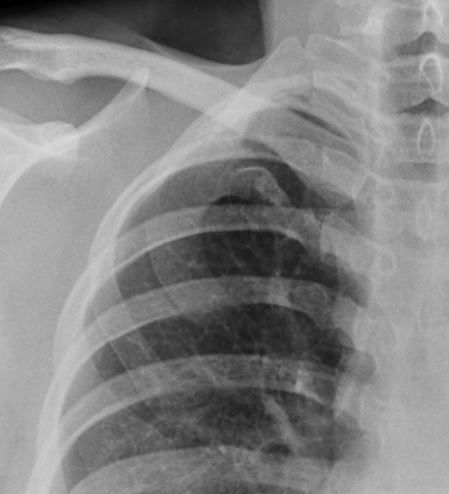

@RadMasterclass

TRAUMA X-RAY 73: Elderly patient. Fall on stairs. Where is the injury? Answer https://t.co/48Twe6e4tc